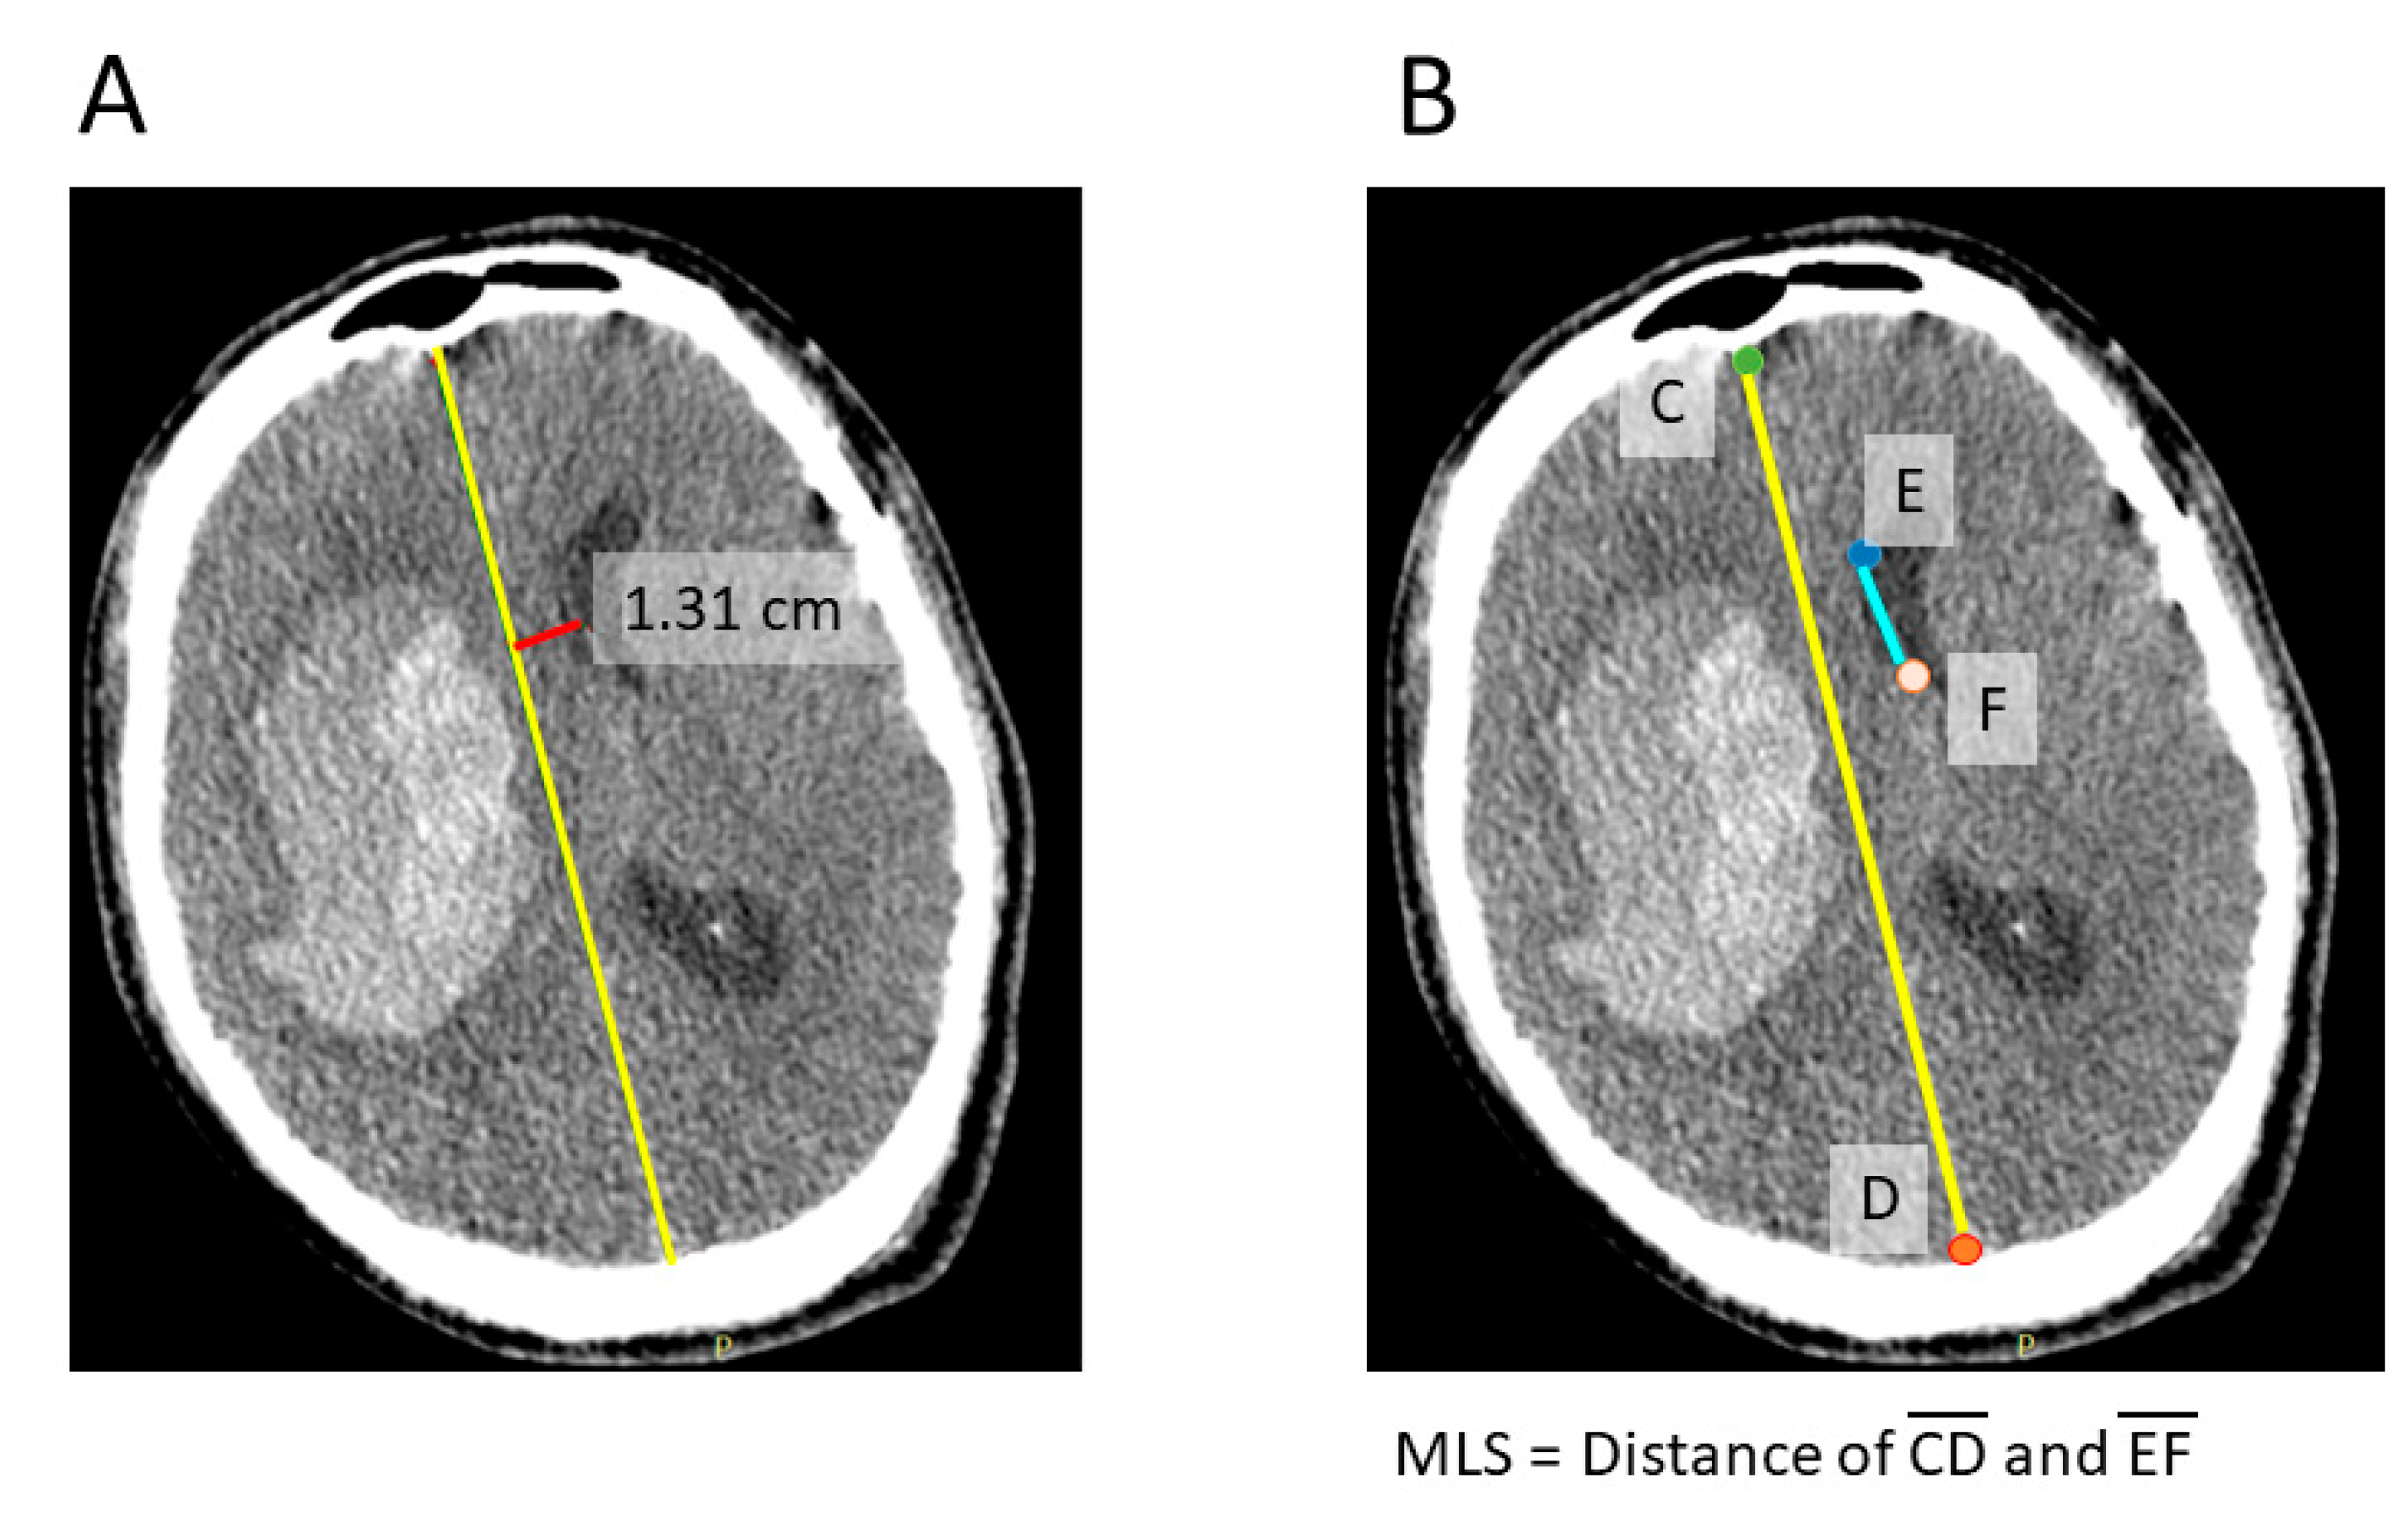

2.2. Neural Network Based Automatic Measurement of the Midline Shift